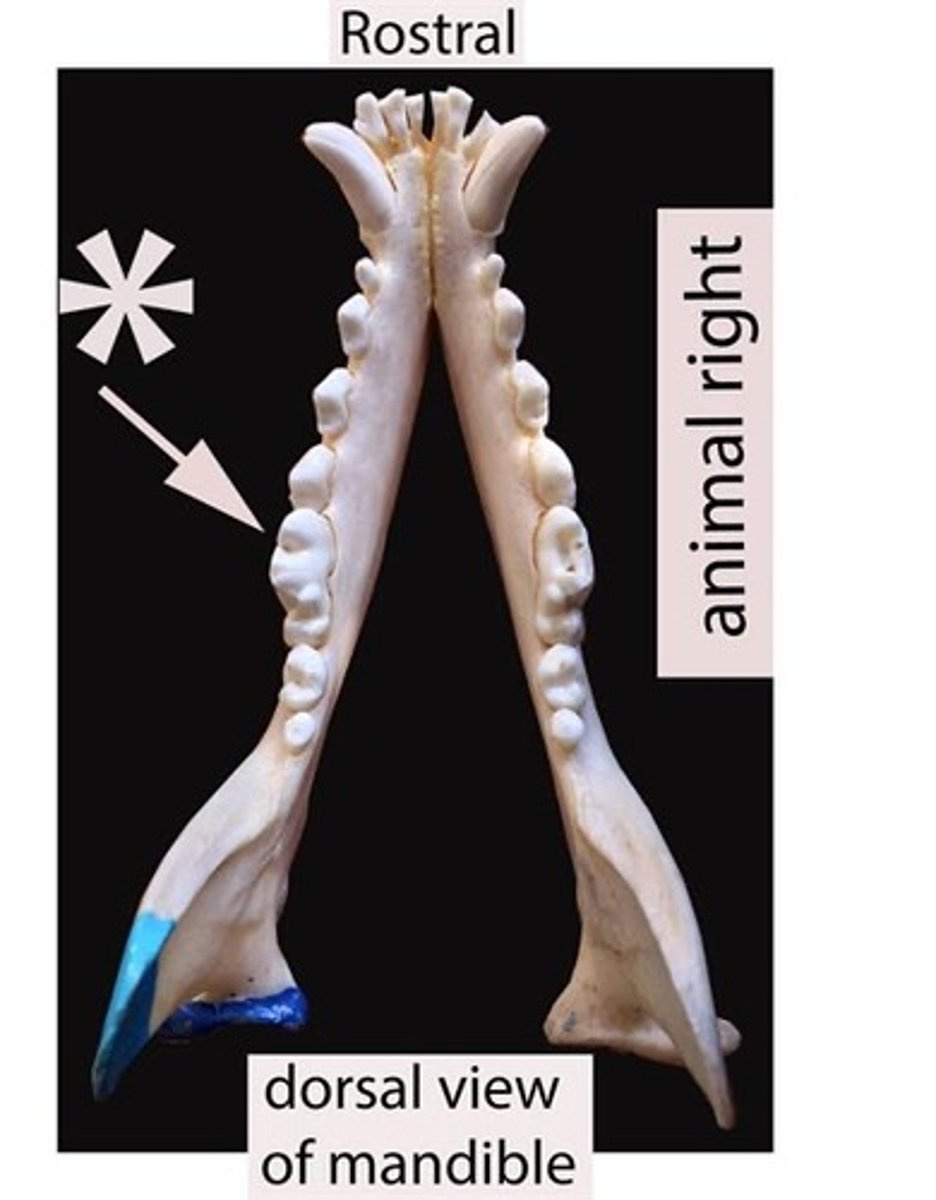

Identify the general type of tooth the arrow is pointing to

Identify the general type of tooth the arrow is pointing to

Identify the general type of tooth the arrow is pointing to

Identify the general type of tooth the arrow is pointing to

Identify the general type of tooth the arrow is pointing to

Identify the general type of tooth the arrow is pointing to

Identify the type of tooth indicated by the arrow.

Identify the type of tooth indicated by the arrow.